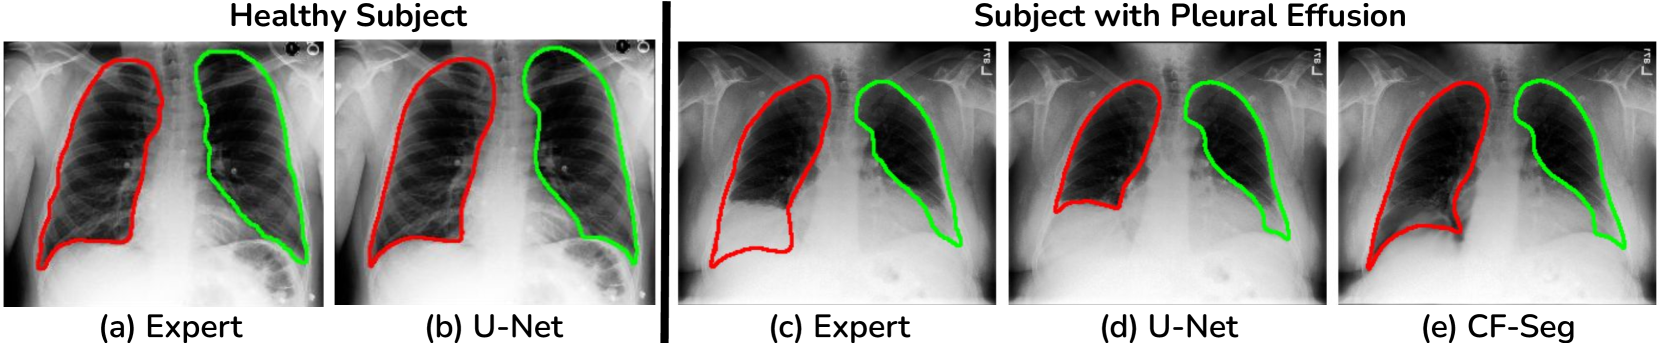

The ability to remove disease patterns from medical images while preserving anatomical structures is crucial for improving anatomical segmentation accuracy. In this work, we explore this possibility using recent advancements in counterfactual image generation models. Fundamentally, counterfactual (CF) images represent ‘what-if’ scenarios, such as: What would the patient’s chest X-ray look like if there was no pleural effusion? In this case, the underlying lung structure should remain unchanged, while the effusion would be removed. This would lead to a clearer anatomical representation, making lung segmentation easier for machine learning models (see Fig. 1).

Refer to caption

Figure 1: Effect of disease on lung segmentation (red - right lung, green - left lung). (a-b) Healthy example: segmentation is relatively easy with high similarity between (a) expert segmentation and (b) automatic segmentation. (c-d) For a subject with pleural effusion, lungs are partially obscured, and segmentation is difficult with major differences between (c) expert segmentation and (d) automatic segmentation. Generating the counterfactual ‘pseudo-healthy’ image removes effusion without altering the underlying anatomy, on which (e) automatic segmentation becomes more similar to (c) expert segmentation.